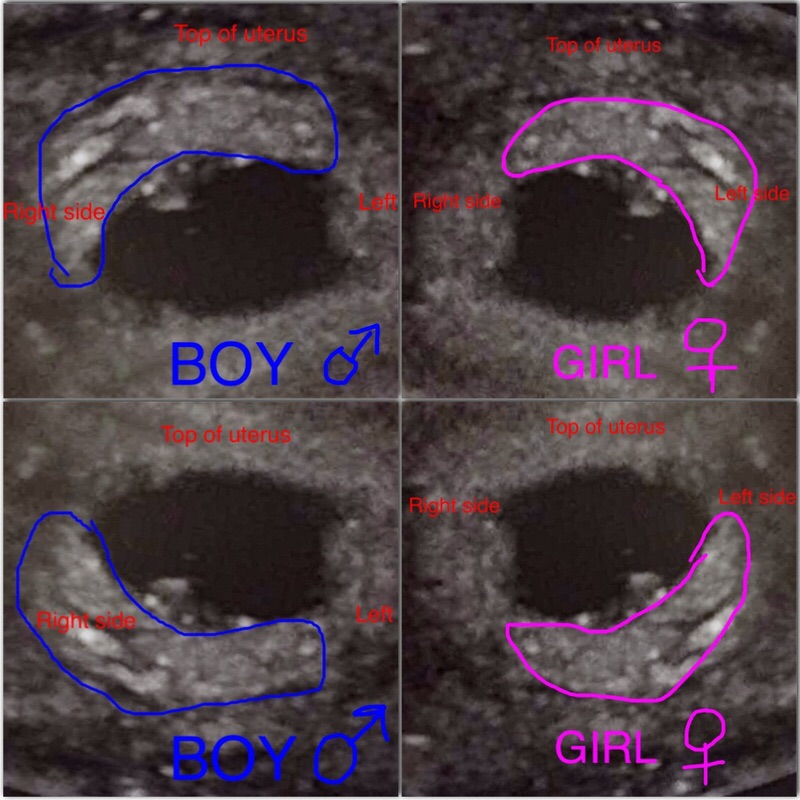

Trans vag u/s @ 6 weeks 0 days. O'd from right ovary.

Attachment 30160